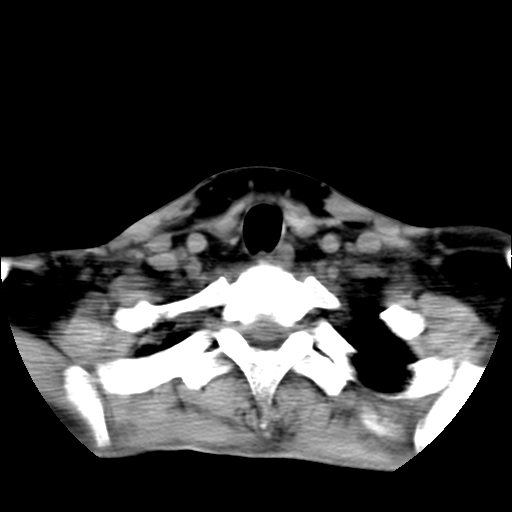

标题: CT24019:男,45岁,发现颈部肿物5个月。 [打印本页]

男,45岁,发现颈部肿物5个月,彩超示:双侧颈部及下颌部软组织增厚。

考虑双侧颈项部良性对称性脂肪增多症。